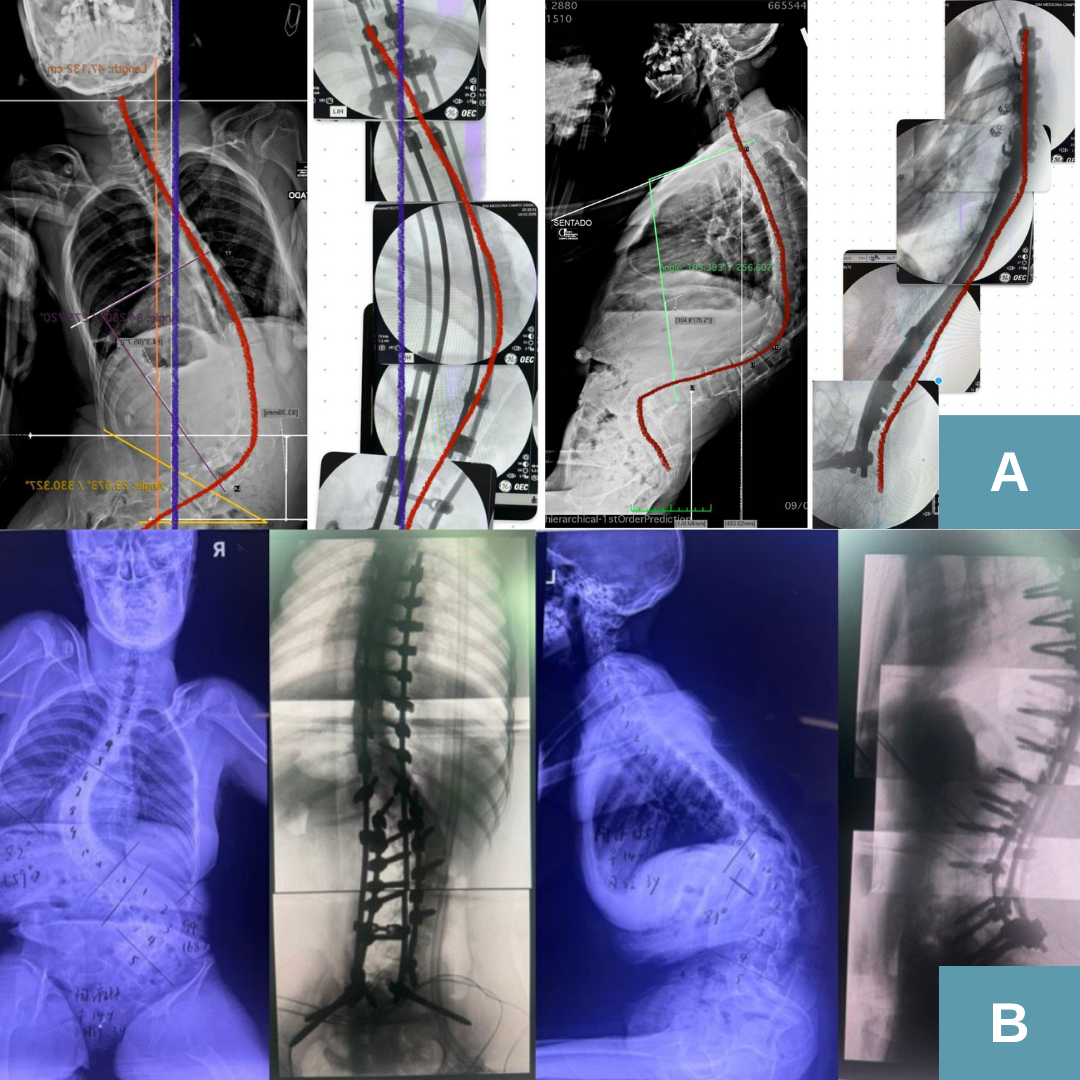

O que é a técnica bipolar?

A técnica bipolar é um tipo de cirurgia utilizada no tratamento da escoliose, principalmente em duas situações: crianças pequenas que ainda estão crescendo e pacientes frágeis, como aqueles com escoliose neuromuscular, paralisia cerebral, distrofias musculares e outras condições genéticas.Diferente da cirurgia tradicional — que exige abrir toda a extensão da coluna, colocar parafusos em todas as vértebras necessárias e instalar duas hastes completas — a técnica bipolar utiliza somente dois pontos de fixação: um na parte superior e outro na parte inferior da coluna.Entre esses pontos, utiliza-se um dispositivo de crescimento, permitindo que a coluna continue a se desenvolver ao longo dos anos.

Como funciona a técnica bipolar?

A técnica bipolar utiliza dois “blocos” de fixação — um superior e um inferior — e um sistema que permite o crescimento natural da coluna entre esses pontos.Em muitos casos, utiliza-se o dispositivo de crescimento chamado Nemost, que funciona como um “macaco de carro”: conforme a criança cresce, ele se estende, mas não volta.Existem duas abordagens:- Técnicas tradicionais de crescimento: exigem retorno ao centro cirúrgico a cada 3 a 9 meses para alongamento.

- Técnica bipolar com Nemost: permite que o crescimento aconteça sozinho, reduzindo o número de cirurgias.